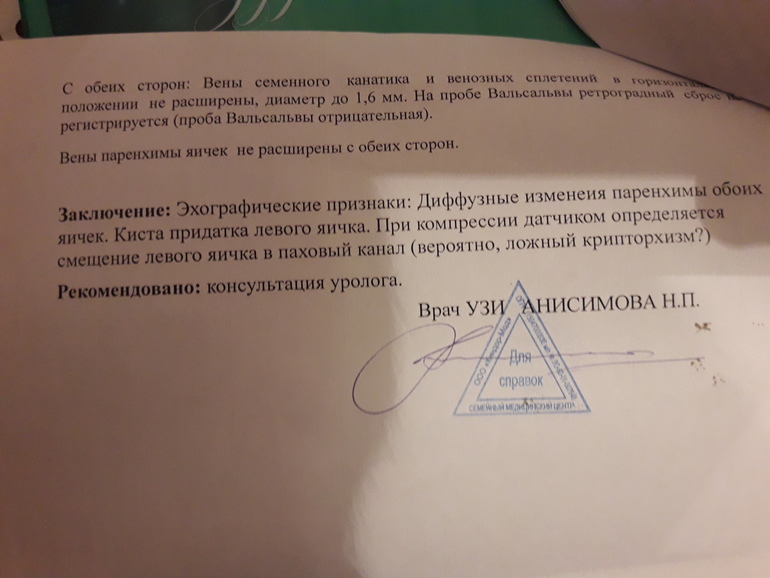

Здравствуйте.сделали узи мошенки мальчику 12 лет.показало диффузные изменения паренхимы яичек.фото прикрепляю(делали 2раза,в разных медцентрах).Подскажите,что это значит.опасаюсь самого страшного.К детскому хирургу попадем только через 3 дня,к андрологу через 4.помогите хоть немного прояснить ситуацию.(изначально обратились к урологу с проблемой задержка мочейспускания-чтобы помочиться ждет некоторое время...)спасибо.